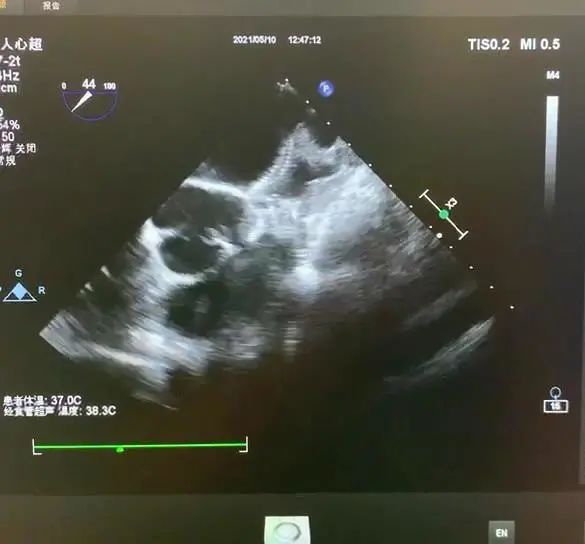

手术在局部麻醉下进行,术中造影显示患者为鸡翅型心耳,DSA下测量左心耳锚定区为22mm,封堵区为27mm。谭冠昶教授与卢谦教授决定选用型号为LT-LAA-2834的LAmbre™左心耳封堵器为患者进行手术封堵。

左心耳造影

锚定区及封堵区测量

DSA与超声显示封堵良好,无残余分流

术中LAmbre™左心耳封堵器牵拉稳定,食道超声下各角度显示封堵完美,符合COST原则。释放后,造影显示左心耳密封效果理想,无任何残余分流,且不影响周围组织结构,手术取得了令人满意的效果。